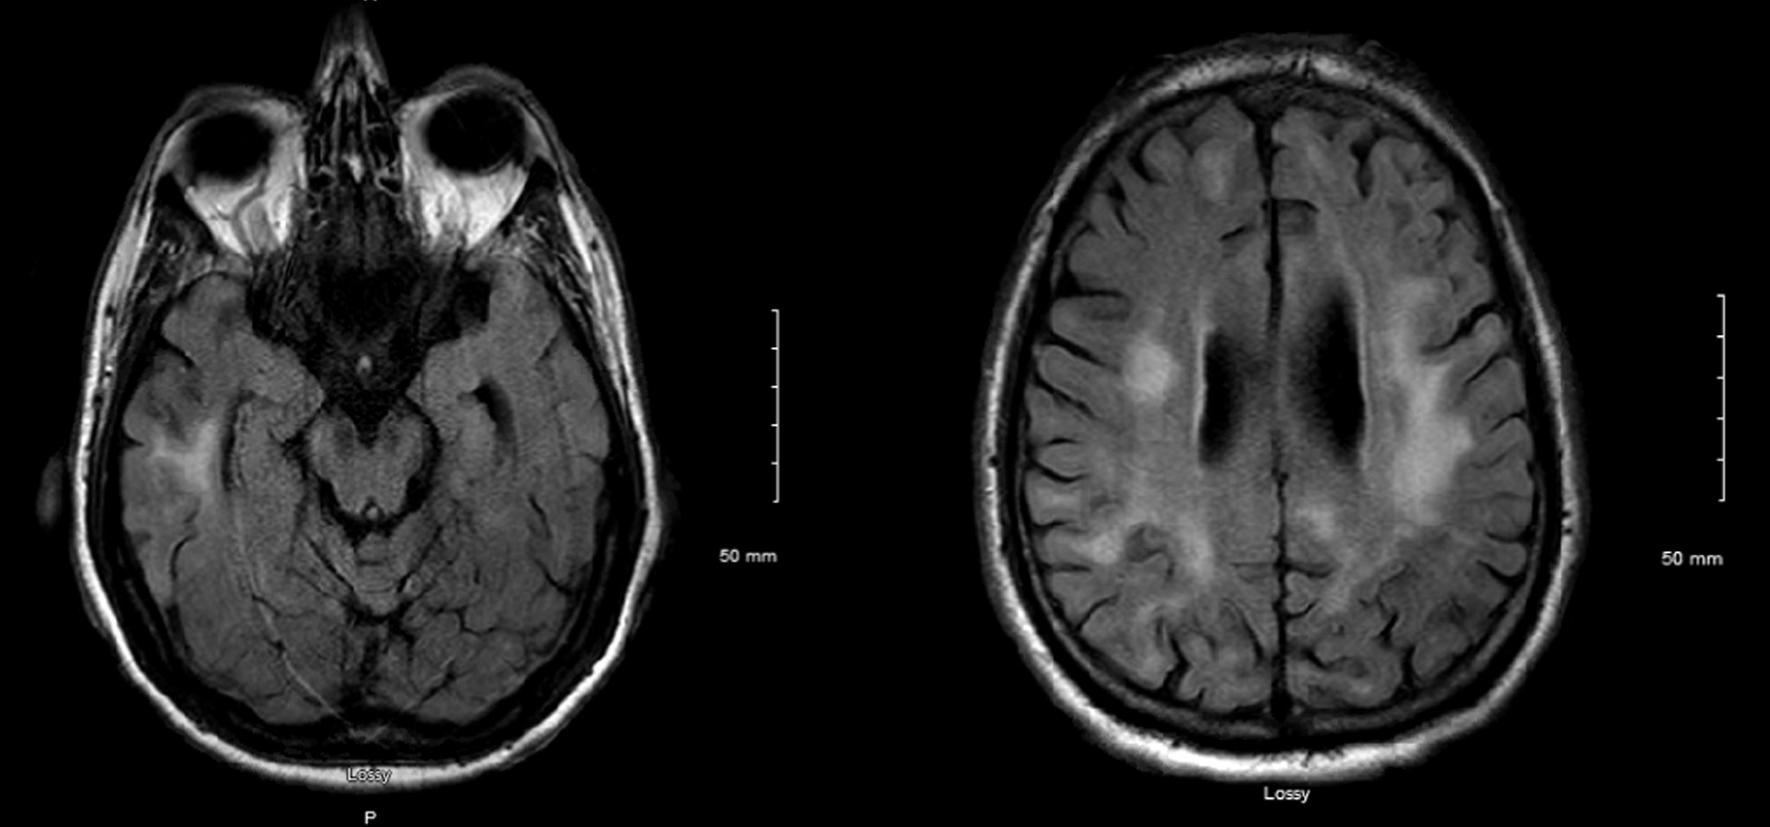

A 70-year-old Caucasian male presented with a subacute onset of cognitive impairment and mood disturbances associated with behavioral changes. Neuroimaging demonstrated high-intensity lesions involving cerebral white matter. Progressive dementia and cognitive decline followed. Multiple possible etiologies are discussed based on the patient presentation and risk factors.

一名 70 岁的白人男性亚急性起病,表现为认知障碍和情绪障碍,伴有行为改变。神经影像学显示累及脑白质的高强度病变。随后出现进行性痴呆和认知能力下降。根据患者的表现和危险因素,讨论了多种可能的病因。